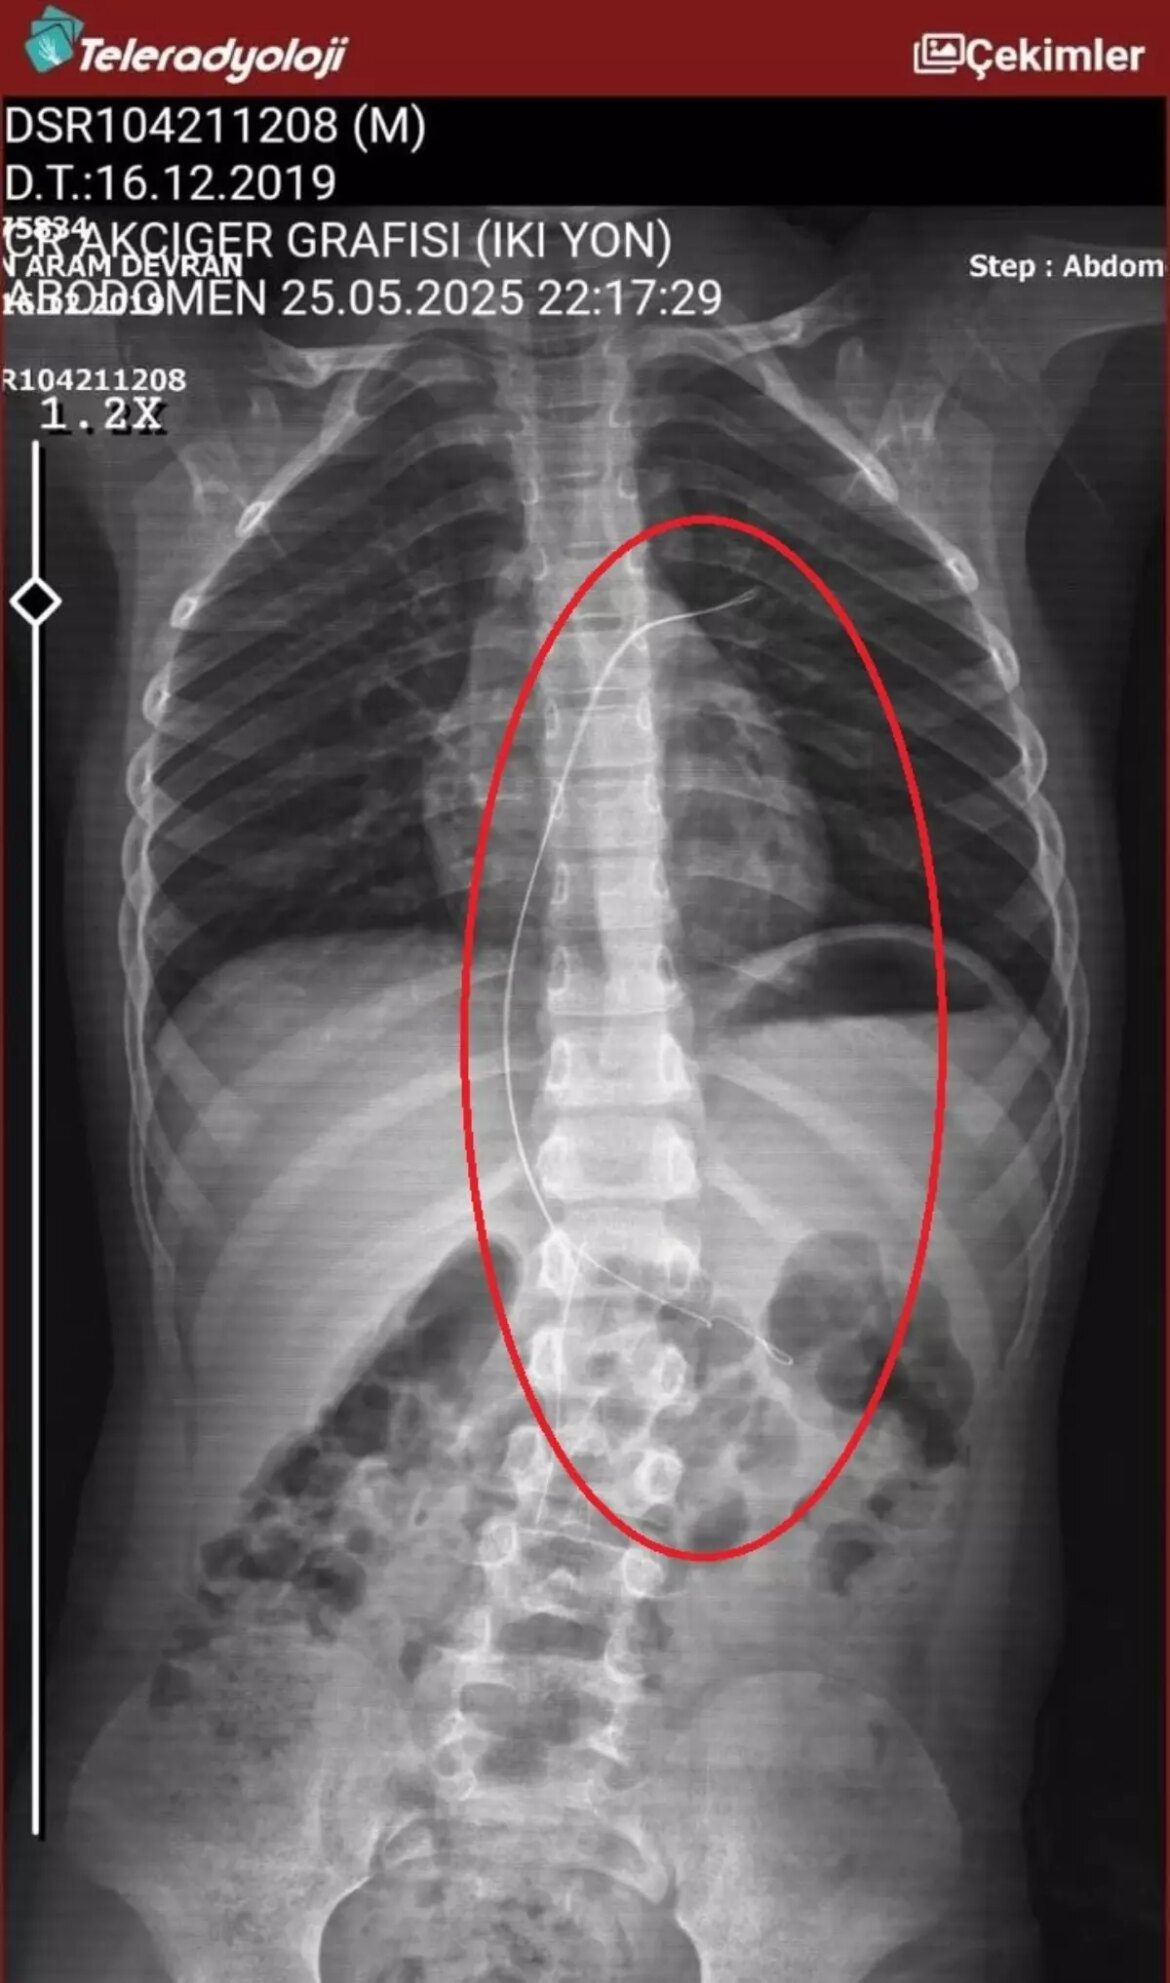

ŞIRNAK’ta piknikte salatalık kesimi yuttuktan sonra öksürük ve kusma şikayetleriyle hastaneye götürülen Aram Devran Ötün’ün (6), 3 yıl evvel Stevens- Johnson sendromu nedeniyle tedavi gördüğü sırada damar yoluna takılan 18 santimetrelik kateterin bedeninde unutulduğu ortaya çıktı. Öğüt, 5,5 saat süren riskli bir ameliyatla kateterden kurtuldu.

Şırnak’ta yaşayan Semra (37) ve Mehmet Ötün (40) çiftinin oğulları Aram Devran Ötün, mayıs ayında piknikteyken salatalık modülü yuttuktan sonra öksürük ve kusma şikayetleri görülünce Şırnak Devlet Hastanesi’ne götürüldü. Burada çekilen röntgen ve MR’da Aram’ın bedeninde kateter unutulduğu görüldü. Diyarbakır’daki Gazi Yaşargil Eğitim ve Araştırma Hastanesi Bayan Doğum ve Çocuk Ek Binası’na sevk edilen Aram, 5,5 saat süren riskli bir ameliyata alınarak 18 santimetre uzunluğundaki kateter çıkarıldı. Ameliyat sonrası yapılan incelemelerde kateterin kalp kapakçığına ve ciğerlerine ziyan verdiği belirlendi.

Oğlunun piknikte salatalık modülü yuttuktan sonra daima öksürmeye ve kusmaya başladığını söyleyen Semra Ötün, “Çocuğum 3 yıl evvel Steven Johnson sendromu hastalığına yakalandı. Milyonda bir görülen antibiyotikten kaynaklı bir hastalık. Hekimler o denli söyledi. Bizi hemen Diyarbakır Dicle Üniversitesi Çocuk Hastanesi kısmına sevk ettiler. 1 ay ağır bakım sürecimiz oldu. 28 gün ağır bakımda, 3 günde serviste kaldı. Damar yolundan, kasıktan serum taktılar. Kateter denilen tel çocuğun bedeninde bırakılıyor. Biz taburcu olduğumuzda fark edilmiyor. 3 yılın sonunda biz bunu fark ettik. Pikniğe gittik. Oğlum salatalık kesimi yuttu ve salatalık modülünden sonra akşama kadar öksürdü. Hiçbir halde durmadı. Kusuyordu. Ben şüphelenmeye başladım. Çocuğum olağan değildi. Sonra eşime danıştım. Akşam 21.00 civarında acile götürdük. Röntgeni ve MR’ı çekildi. Tuhaf bir şey olduğunu anladık. Doktor röntgeni gösterdi. Tel kalmıştı. Çok berbat bir biçimde. Acil tabibi sinema çektikten sonra bize bir tel kesimini gösterdi. Bizi bekletmeden Diyarbakır’a sevkimizi verdiler. Diyarbakır Gazi Yaşargil Eğitim ve Araştırma Hastanesi Bayan Doğum ve Çocuk Ek Binası’na gittik. Çocuğun kasıklarından anjiyo yolu ile teli çıkaracaklarını lakin riskli bir ameliyat olduğunu söylediler. O süreçte çocuk sahiden daima yoruluyordu. İkide bir oturuyordu. ‘Anne çok yoruldum, karnım ağrıyor’ diyordu. Ben ağrı kesiciler ile geçiştirmeye çalışıyordum. Bu telin 3 yıl boyunca çocuğumda kaldığını öğrendim. Ailece yıkıldık” diye konuştu.

“Çocuğum yaklaşık 5,5 saat ameliyatta kaldı. Ameliyata giren doktor kötü bir şekilde çıkıyordu. Çok güç bir yerde olduğunu ve yorulduklarını söylüyordu. Materyal atıyoruz, gereç geliyor tel hiçbir gelmiyor, dedi. Sonra en son bir doktor çıktı, ‘İki seçeneğimiz var. ya açık kalp ameliyatı ya da çocuk ömür uzunluğu o tele maruz kalacak’ dediler. Her iki seçenekte benim için çok acıydı. Sonra profesör girdi ameliyatına başardılar. Çıkardılar. Şu anda kalp kapakçığında sorun varmış. Çocuğum bundan ötürü tedavi oluyor. Çok acılı günler geçirdik. Çok güç günler geçirdik. Bizim canımız yandı kimsenin canı yanmasın. Tabipler söylediğinde inanamadım. Şok oldum. Zira çocuğum 3 sene boyunca takipli hasta olduğumuz için daima Diyarbakır’a, Ankara’ya daima gidip geliyoruz. İnanamadım ben. Kendi gözlerimle görmeyene kadar inanmadım. Çok makus olduk.”